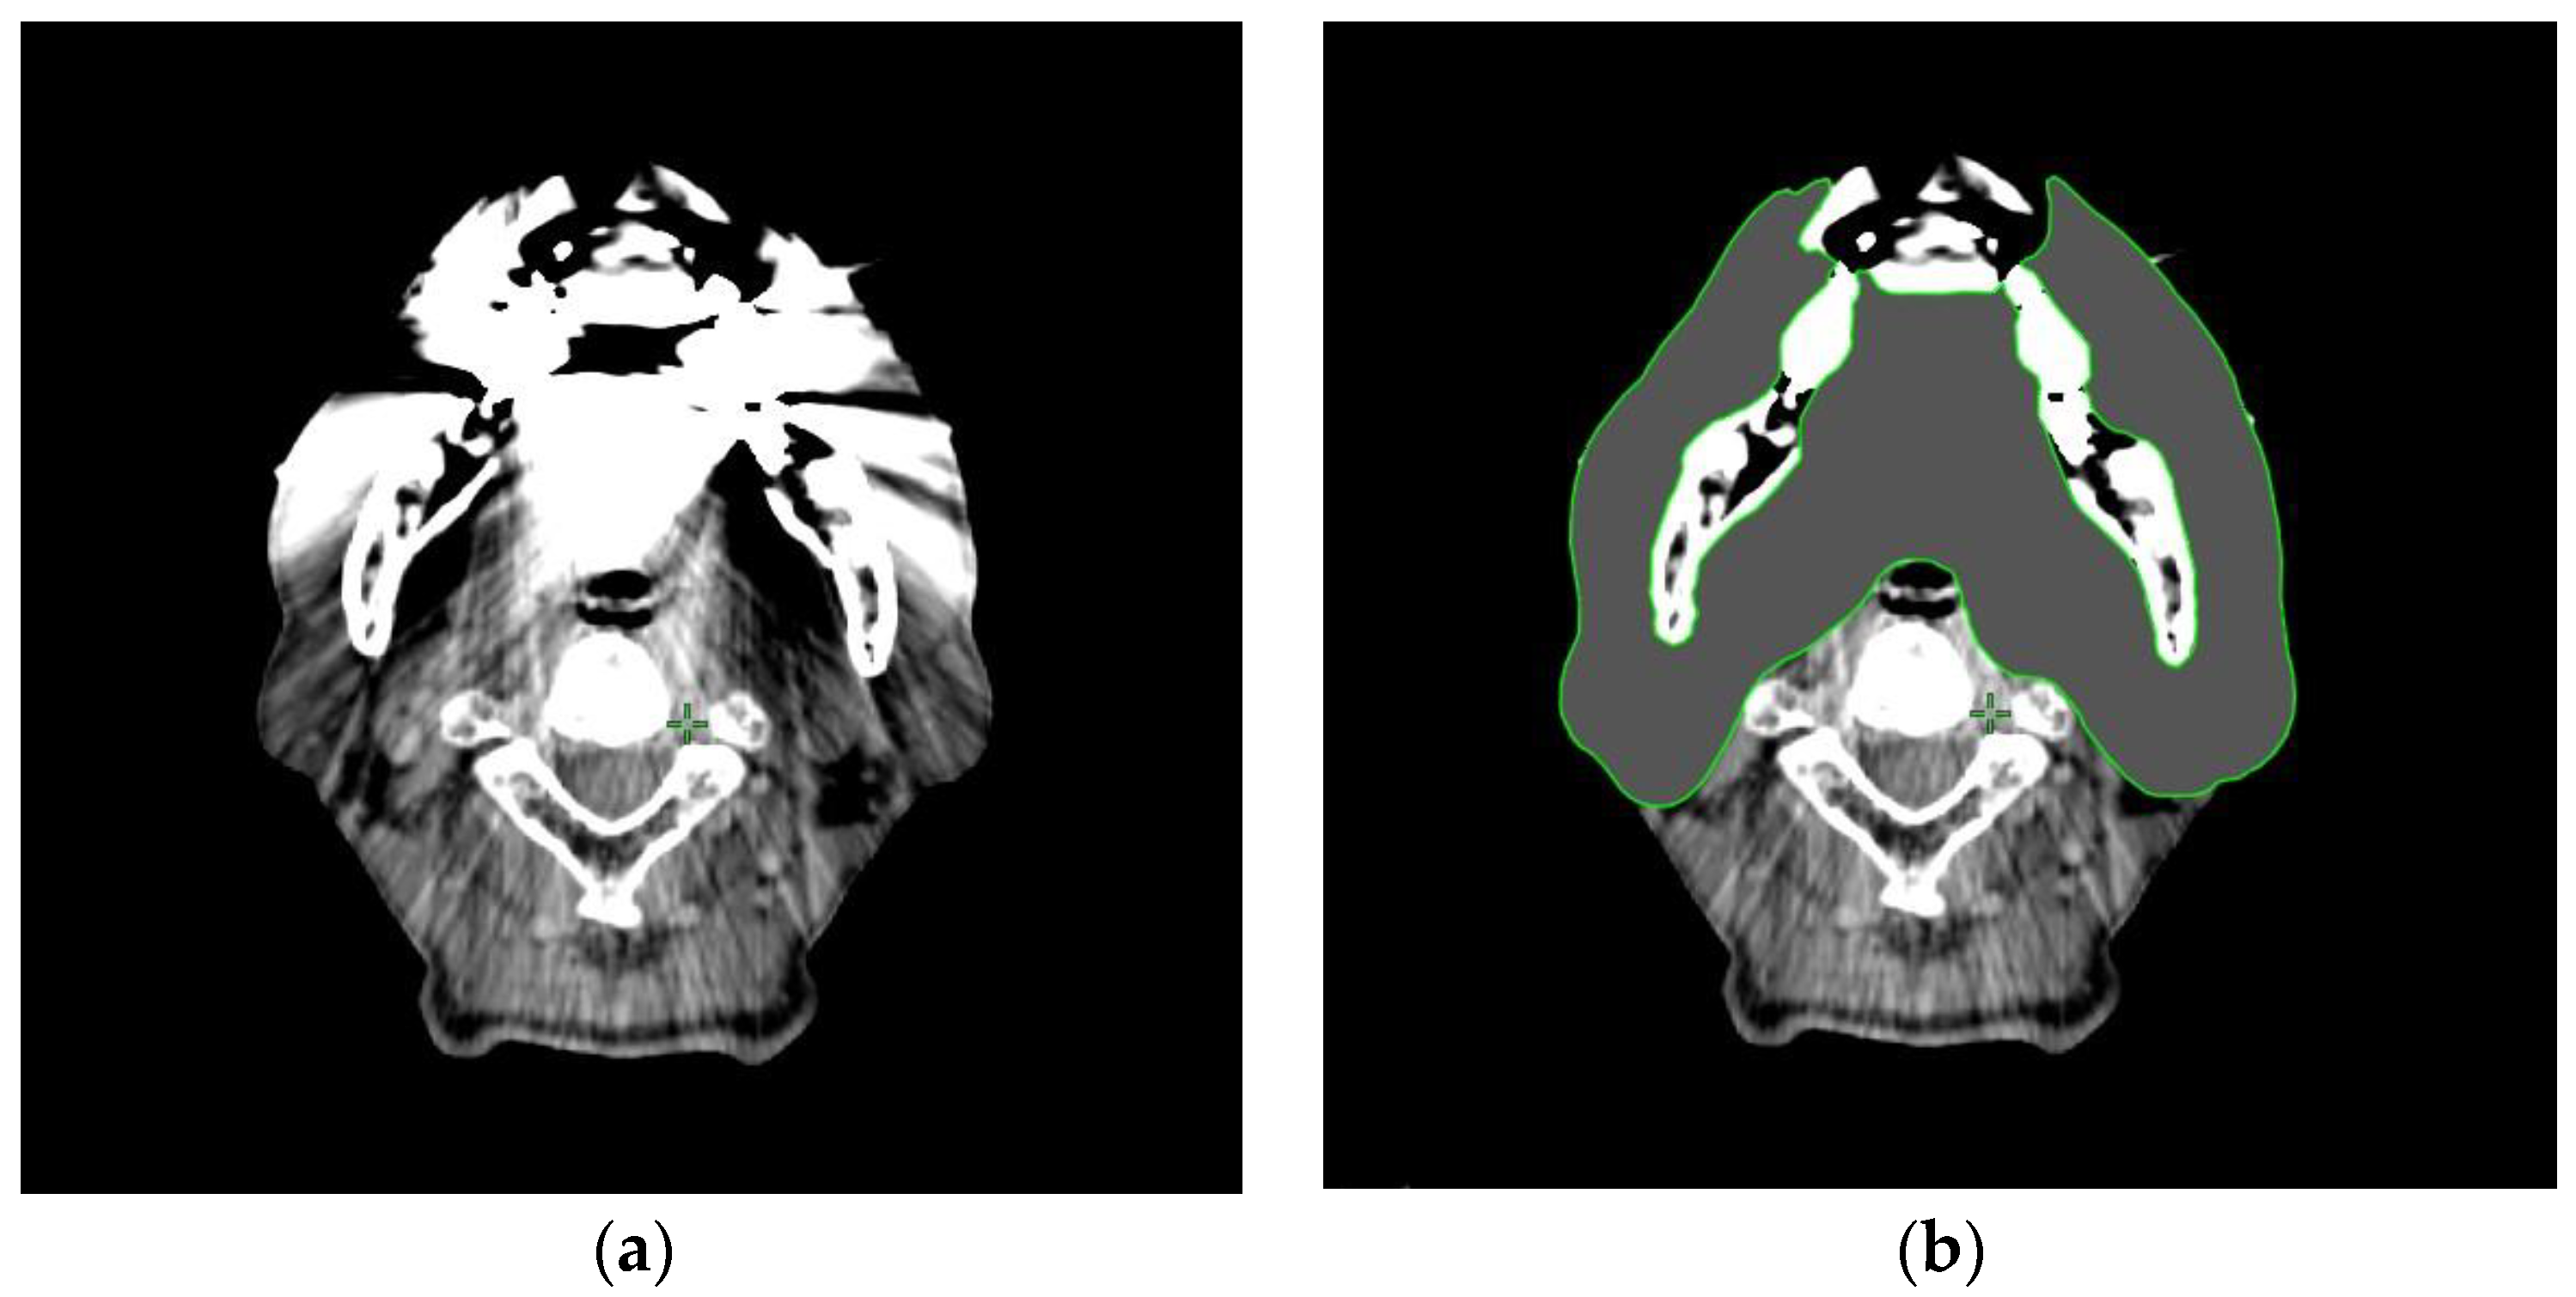

2.3. Contouring of the Dental Metal Artifacts Area